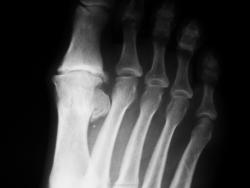

Один из методов лечения поперечного палоскостопия с выраженым дефартрозом 1 пл-ф суст. Операция Вредена-Мейо+ операция Брандеса+формирование поперечной связки стопы+протезирование. Померяйте какой сейчас Hallux valgus, опишите состояние культи и протеза.